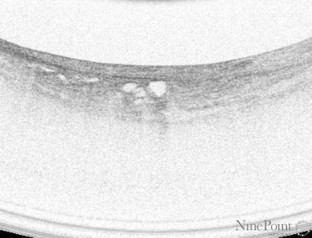

Fig. 1

The authors would like to thank Mr. Pat MacCarthy of NinePoint Medical for supplying image 1–3 and Dr. Prateek Sharma of Kansas City VA medical center for supplying image 4–5 for this manuscript.